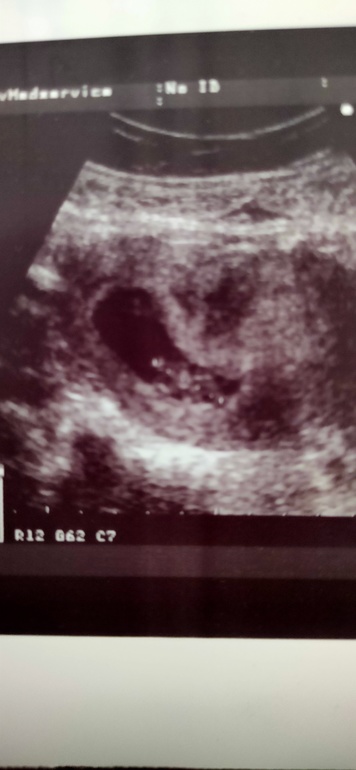

Была на УЗИ, срок 9-10 недель, а КТР всего 26 мм, истерю..... Должен быть 30-40 на этом сроке.

2 недели назад был 17 мм.

И по фото плодное яйцо очень сплюстнуто, горе-узистка сказала " на одном снимке вроде тонус есть, а на другом вроде бы нет"!!!!

30-40 мм кто это норма для 10-11 недель соответственно, кто вашего малыша на 9 нед 4 дня, все по сроку)